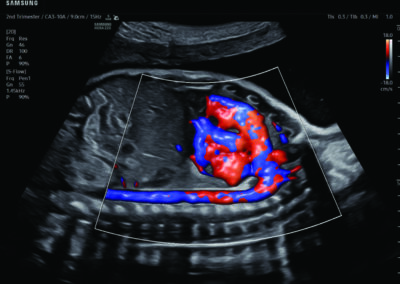

Procedural Services

Comprehensive, advanced and expert MFM care for high-risk pregnancies

- Fetal anomalies